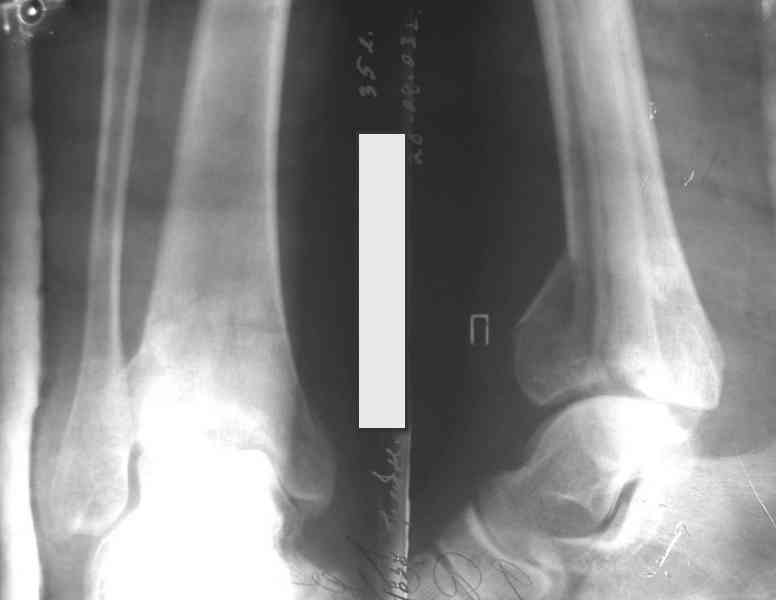

Посылаю результат лечения предыдущего больного через год.

На рентгенограммах типичный перелом пилона по типу С-3. есть опыт до 100 открытых опреаций у нас в клинике. 20 примерно в год. Принцип один -все внутрисуставные переломы нуждаются в открытой репозиции и внутренней стабильной фиксации. При поступлении КТ не надо, так как получается только нагромождение костей. Истинной картины нет. Главное восстановить длину малоберцовой кости - это ключ к успеху. При поступлении меньше всего надо думать о сосудистых расстройствах, т.к. сама операция и репозиция даже сначала частичная даёт улучшение сосудитых нарушений. Причём очень быстро. Операция в 2этапа. При поступлении доступ позади наружной лодыжки, причём обязательно. После этого репозиция малоберцовой кости и фиксация пластиной 1/3 трубки под винт 3,5. Дренаж и любой аппарат наружной фиксации. Затем после спадения отёка на 5-7-10 день аппрат снимается и дугообразный разрез спереди от медиальной лодыжки 10-12 см. Главной чтобы расстояние между 1 и вторым разрезом было не меньше 7-8 см. Тогда не будет некрозов лоскутов. Таранная кость используется как матрица на неё укладываются отломки и фиксируются пицами. Ренг-контроль. Отломки лежат все отдельно, но ничего не высыпется. При переломах С-3 всегда нужна костная пластика (из крыла). Фиксация пластиной лист клевера простой или LCP. Гипс не нужен. Дренаж до 48 часов. Операция длится 3-4 часа обязательно без жгута. Посылаю примерно такой же случай.